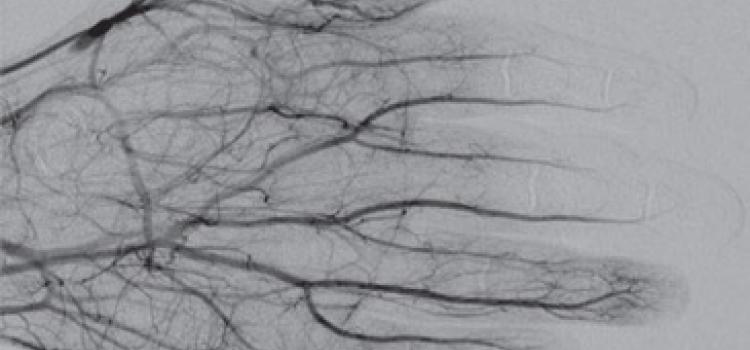

Interventional radiology uses tools like angiography X-ray systems to provide minimally invasive medical diagnosis and treatment using images.